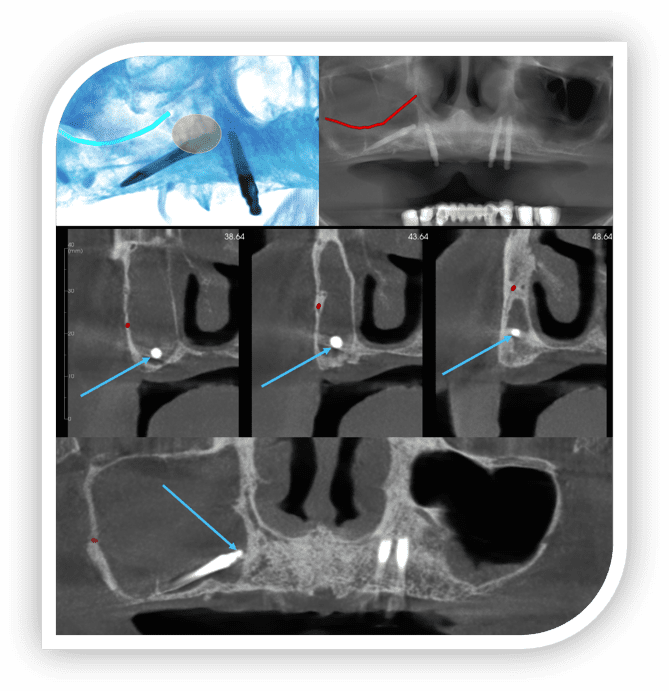

Dental Imaging Diagnostics

Custom CBCT interpretations, surgical guides, consultation, and CE — all delivered by Oral & Maxillofacial Radiologists, tailored for today’s dental practice.

CBCT Cephalometric Tracing and Analysis

Add cephalometric measurements and tracings to your large FOV CBCT reports for $40 per case. Custom analysis sets available with a one-time $499 setup fee. No setup fee for stock analysis. Learn more here.